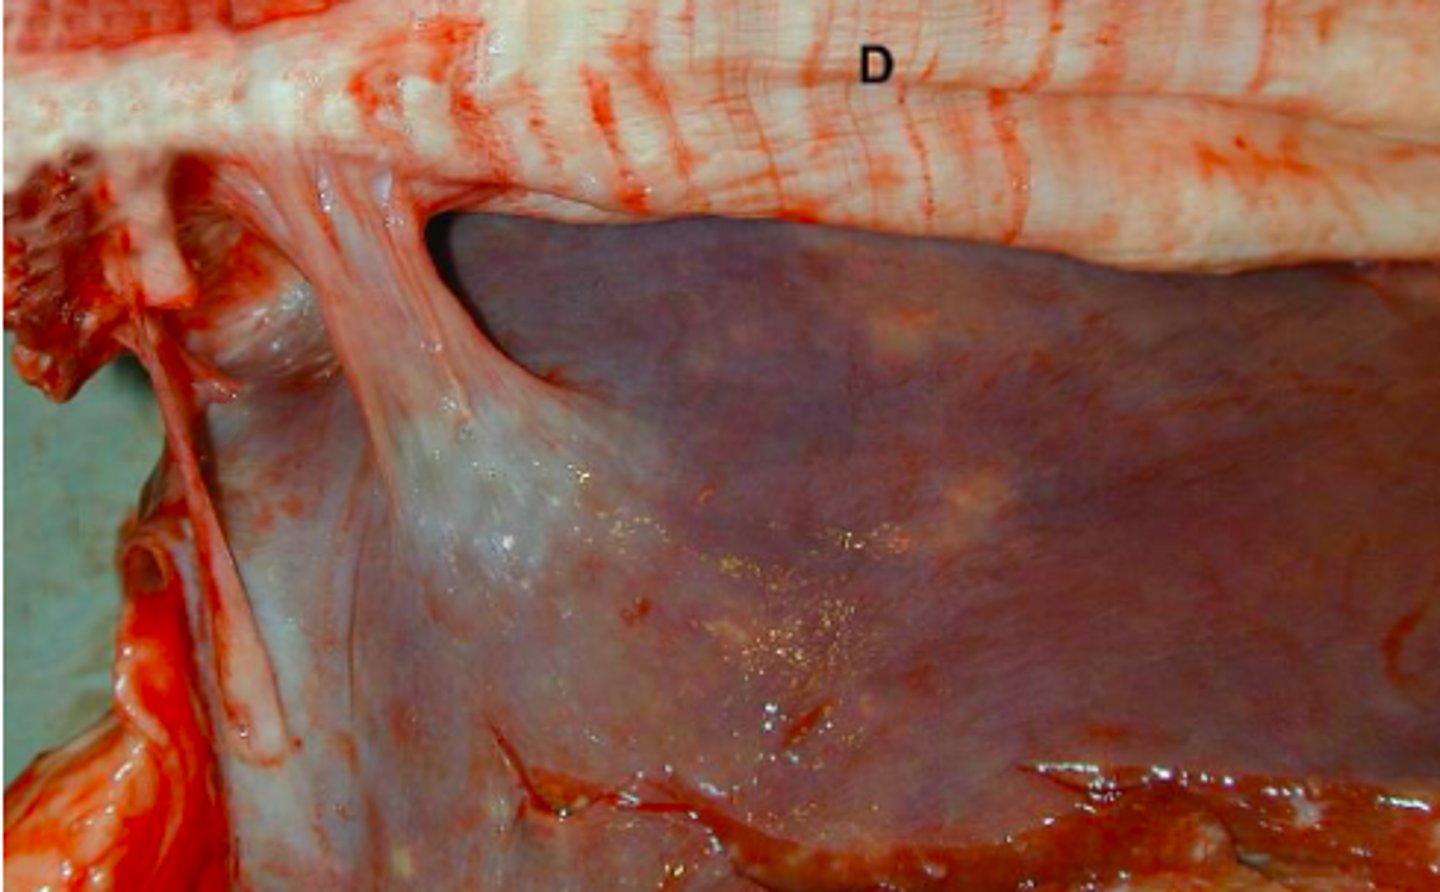

Kronisk peritoneal og perihepatisk cystecerkose

Ætiologi: Cysticerus tenuicollis

Lever fra får (med diaphragma, D), hvad er den patoanatomiske diagnose og ætiologien?

Lever fra kvæg og diaphragma (d), hvad er den patoanatomiske diagnose?

Kronisk, lokal, subfrenisk absces m. fibrøs adhæsion

Lever fra kvæg og diaphragma (d), hvad er den patoanatomiske diagnose?